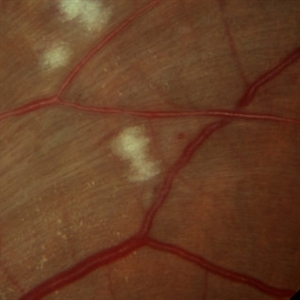

Cotton Wool Spots

Mar 1 2014 by Homayoun Tabandeh, MD, FASRS

Cotton wool spots in a patient with hypertension and diabetes

Condition/keywords: cotton wool spots, diabetic retinopathy, hypertensive retinopathy